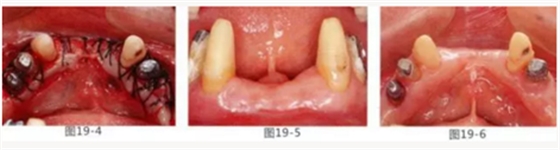

有少數(shù)牙體殘存的病例,需要進行修復處理,將基牙和鉤牙部位的牙周袋去除以及對頰舌側進行FGG(游離齦移植)來獲取附著齦的病例

圖19-1 右下3,4,左下3,4,5殘存牙頰側面照。唇頰側沒有附著齦。

圖19-2 同部位的舌側面照。雖然有1mm左右角化牙齦,但是進行預測切開的話,會使角化牙齦完全消失。

圖19-3 左下3,4,5部位進行FGG(游離齦移植)去除牙周袋以及獲得附著齦。同時進行骨外科處理。相反側也進行同樣的處理。

圖19-4 將移植片固定于右下3,4左下3,4,5的舌側骨膜,并進行牙周袋去除以及獲得附著齦。

圖19-5,6 術后1個月唇舌側的愈合狀態(tài)。唇舌側都獲得了足夠附著齦。